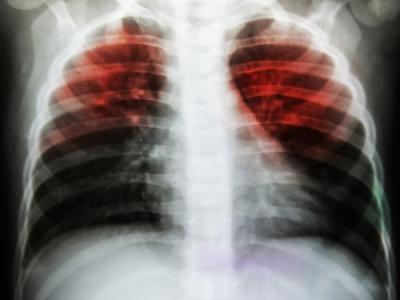

2) टीबी

तपेदिक (टीबी) भारत की प्रमुख सार्वजनिक स्वास्थ्य समस्याओं में से एक है। WHO के अनुमान के अनुसार, भारत में दुनिया का सबसे बड़ा तपेदिक महामारी है। इंडियन रेड क्रॉस सोसाइटी (IRCS) यह सुनिश्चित करने में एक महत्वपूर्ण भूमिका निभा रही है कि टीबी के मामलों का सफलतापूर्वक इलाज किया जाए और रोगियों के खिलाफ भेदभाव और भेदभाव को समाप्त किया जाए।